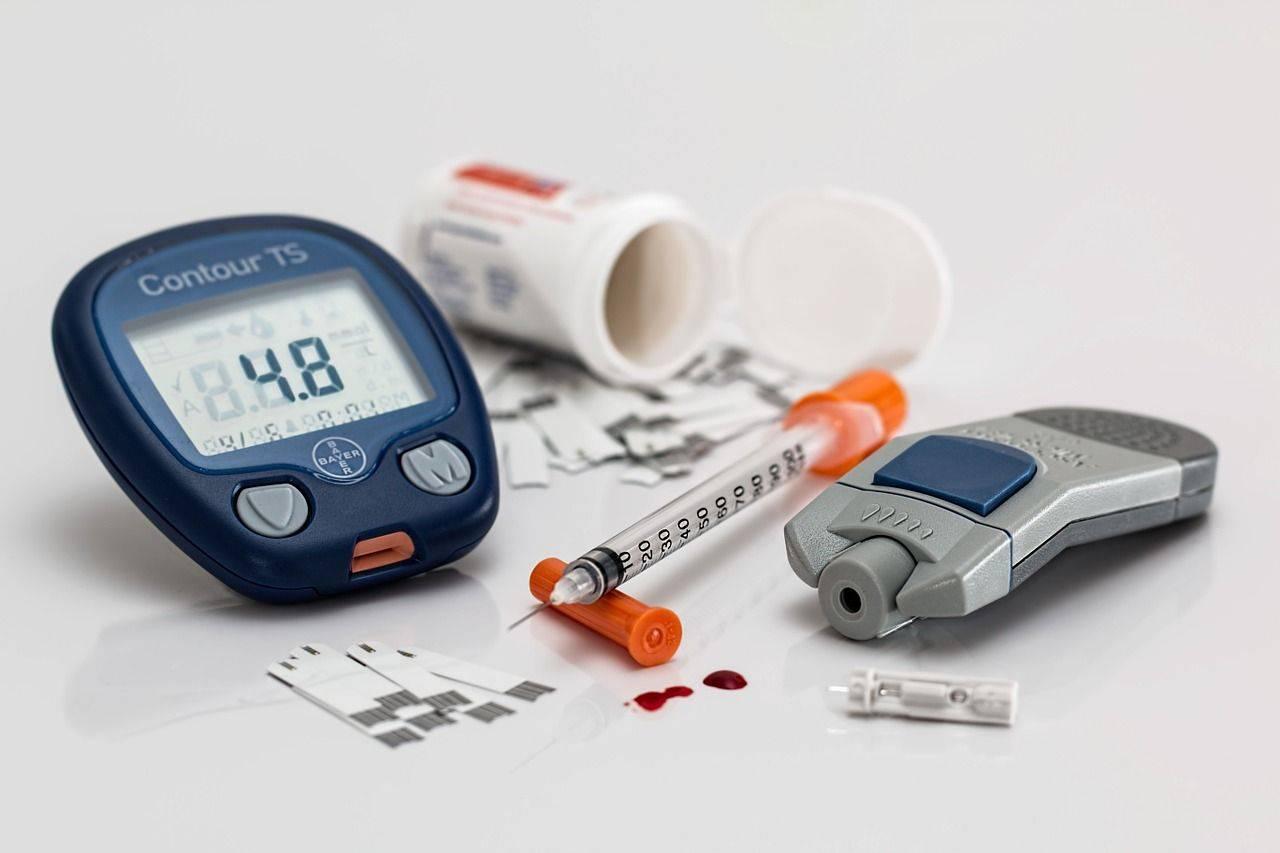

Le diabète sucré est une maladie endocrinienne grave avec un déficit insulinique grave.